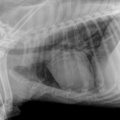

Cuattro DR HD è l'ultimo sistema radiografico digitale ad alta definizione per piccoli animali ed equini prodotto dal fornitore leader di soluzioni radiografiche digitali veterinarie.

Innovativo, veloce, efficace, sicuro e ancora più brillante: l'ultimo sistema a raggi X, Cuattro DR HD soddisfa i più alti standard nella diagnostica radiografica veterinaria.

• Visualizza i dettagli come mai fino ad ora : 17x17'’ 100 microns High definition detectors combinati con la migliore tecnologia post-elaborazione nel nostro software per immagini di altissima qualità